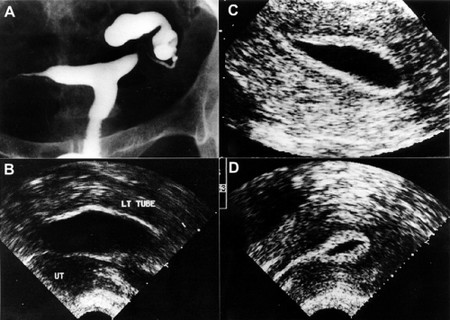

步骤7:查查“管道”。

检查输卵管是否通畅,可以使用输卵管通液、子宫输卵管造影、宫腔镜下输卵管通液等。这些检查应该在月经结束后的3~7天内进行,并且应该遵循简单先于复杂,非侵入性先于侵入性的原则。